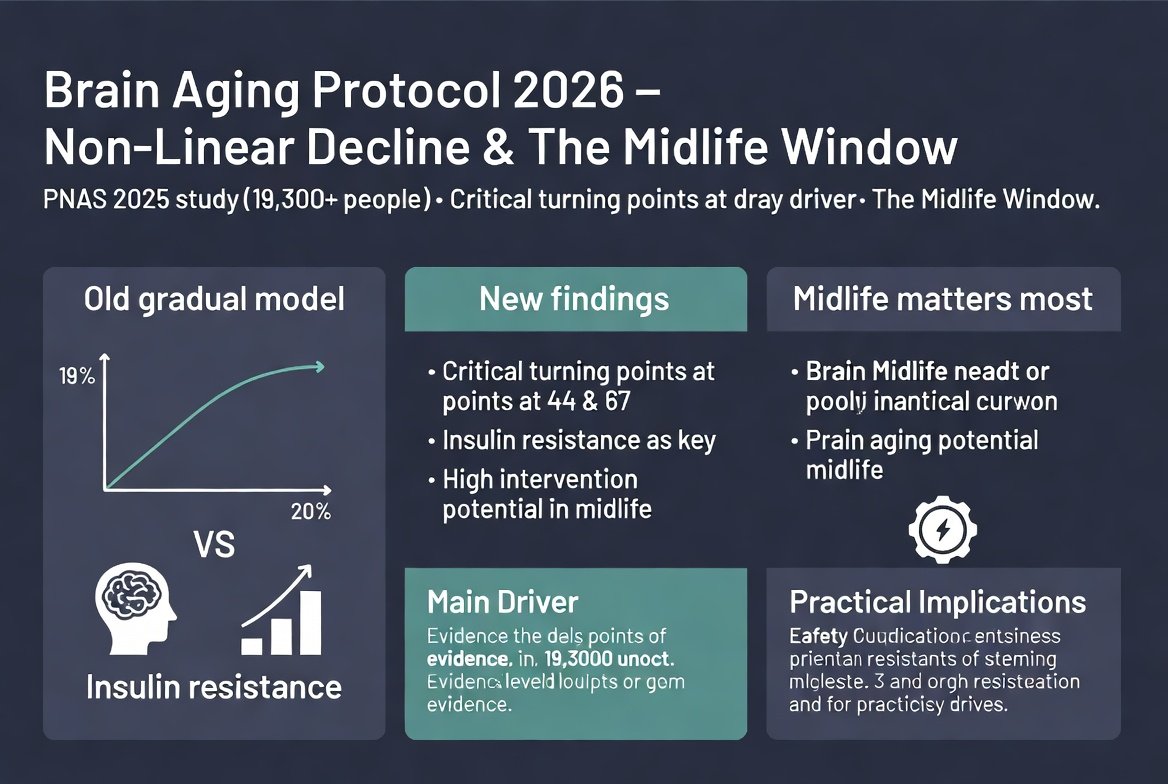

מוח

מוח

במשך עשורים הנחנו שהמוח שלנו מזדקן באיטיות, קצת בכל שנה, כמו שעון שמאט בהדרגה. מחקר חדש שפורסם ב-PNAS במרץ 2025, שניתח את המוח של מעל 19,300 אנשים, הו...